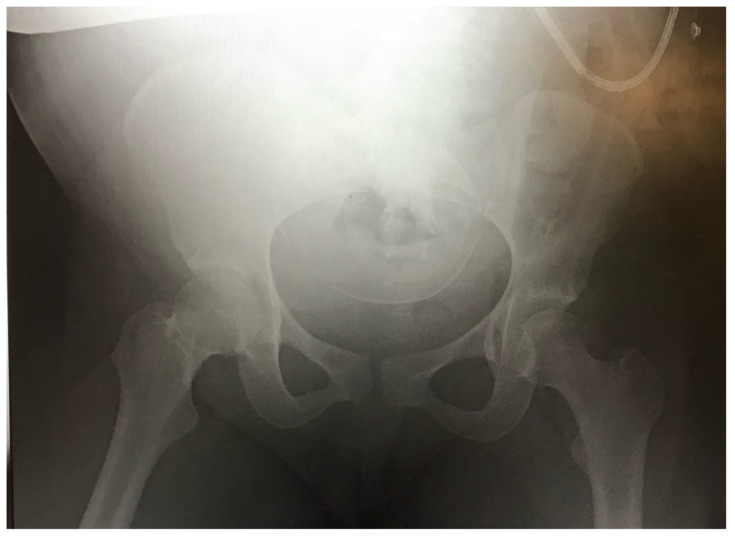

Introduction: Emergency and trauma surgery practitioners routinely perform primary and secondary surveys as a systematic approach to trauma care. While this approach has broad applications, clinicians must also be versed in the nuances of caring for special populations in trauma. One such example is the obstetric patient. The incidence of trauma in pregnancy is increasing and is now the leading cause of non-obstetrical maternal death in the United States.1 Optimal maternal resuscitation depends on an understanding of the significant anatomic and physiologic changes of pregnancy and their influence on airway, breathing, and circulation.2,3,4This case presents a blunt polytrauma with unstable pelvic and lower extremity fractures precipitating hemorrhagic shock and the need for blood product transfusion. Learners must quickly adapt their clinical acumen and consider the influence of an obviously gravid patient on their resuscitation. Implementing and practicing the required skills allows for delivery of high-quality care. This session ensures that learners have a well-rounded understanding of scenarios that could occur in the resuscitation of a pregnant trauma patient.

Educational objectives: At the completion of this simulation participants will be able to 1) perform primary and secondary trauma surveys, 2) assess the neurovascular status of a tibia/fibula fracture, 3) appreciate anatomic and physiologic differences in pregnancy, 4) appropriately order analgesia and imaging, 5) recognize and treat hemorrhagic shock, 6) perform an extended focused assessment with sonography in trauma exam (eFAST) in undifferentiated hemorrhage, 7) identify a displaced pelvic fracture and properly apply a pelvic binder, and 8) obtain and interpret fetal heart rate using ultrasound.